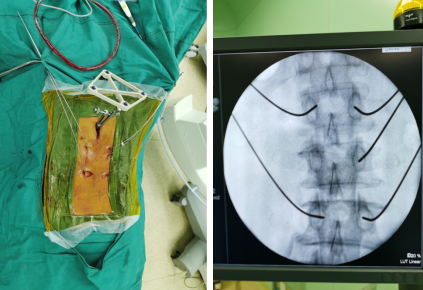

体表定位,安装示踪器,扫描传送、规划钉道

最终,尚军主任孟磊副主任医师团队在骨科机器人定位下,通过3D图像确定手术中椎弓根螺钉的进钉点、置钉方向以及置钉深度。接着,在机器人系统导航下,机械臂精准移动到置钉位置,医生只在置钉部位切开约1.2cm切口,沿着机械臂所指方向钻入导针,并沿导针置入椎弓根即可,从而使椎弓根螺钉能够以最理想化的方式打入,保证了患者的安全和手术的有效性。

机械臂辅助钻入导针